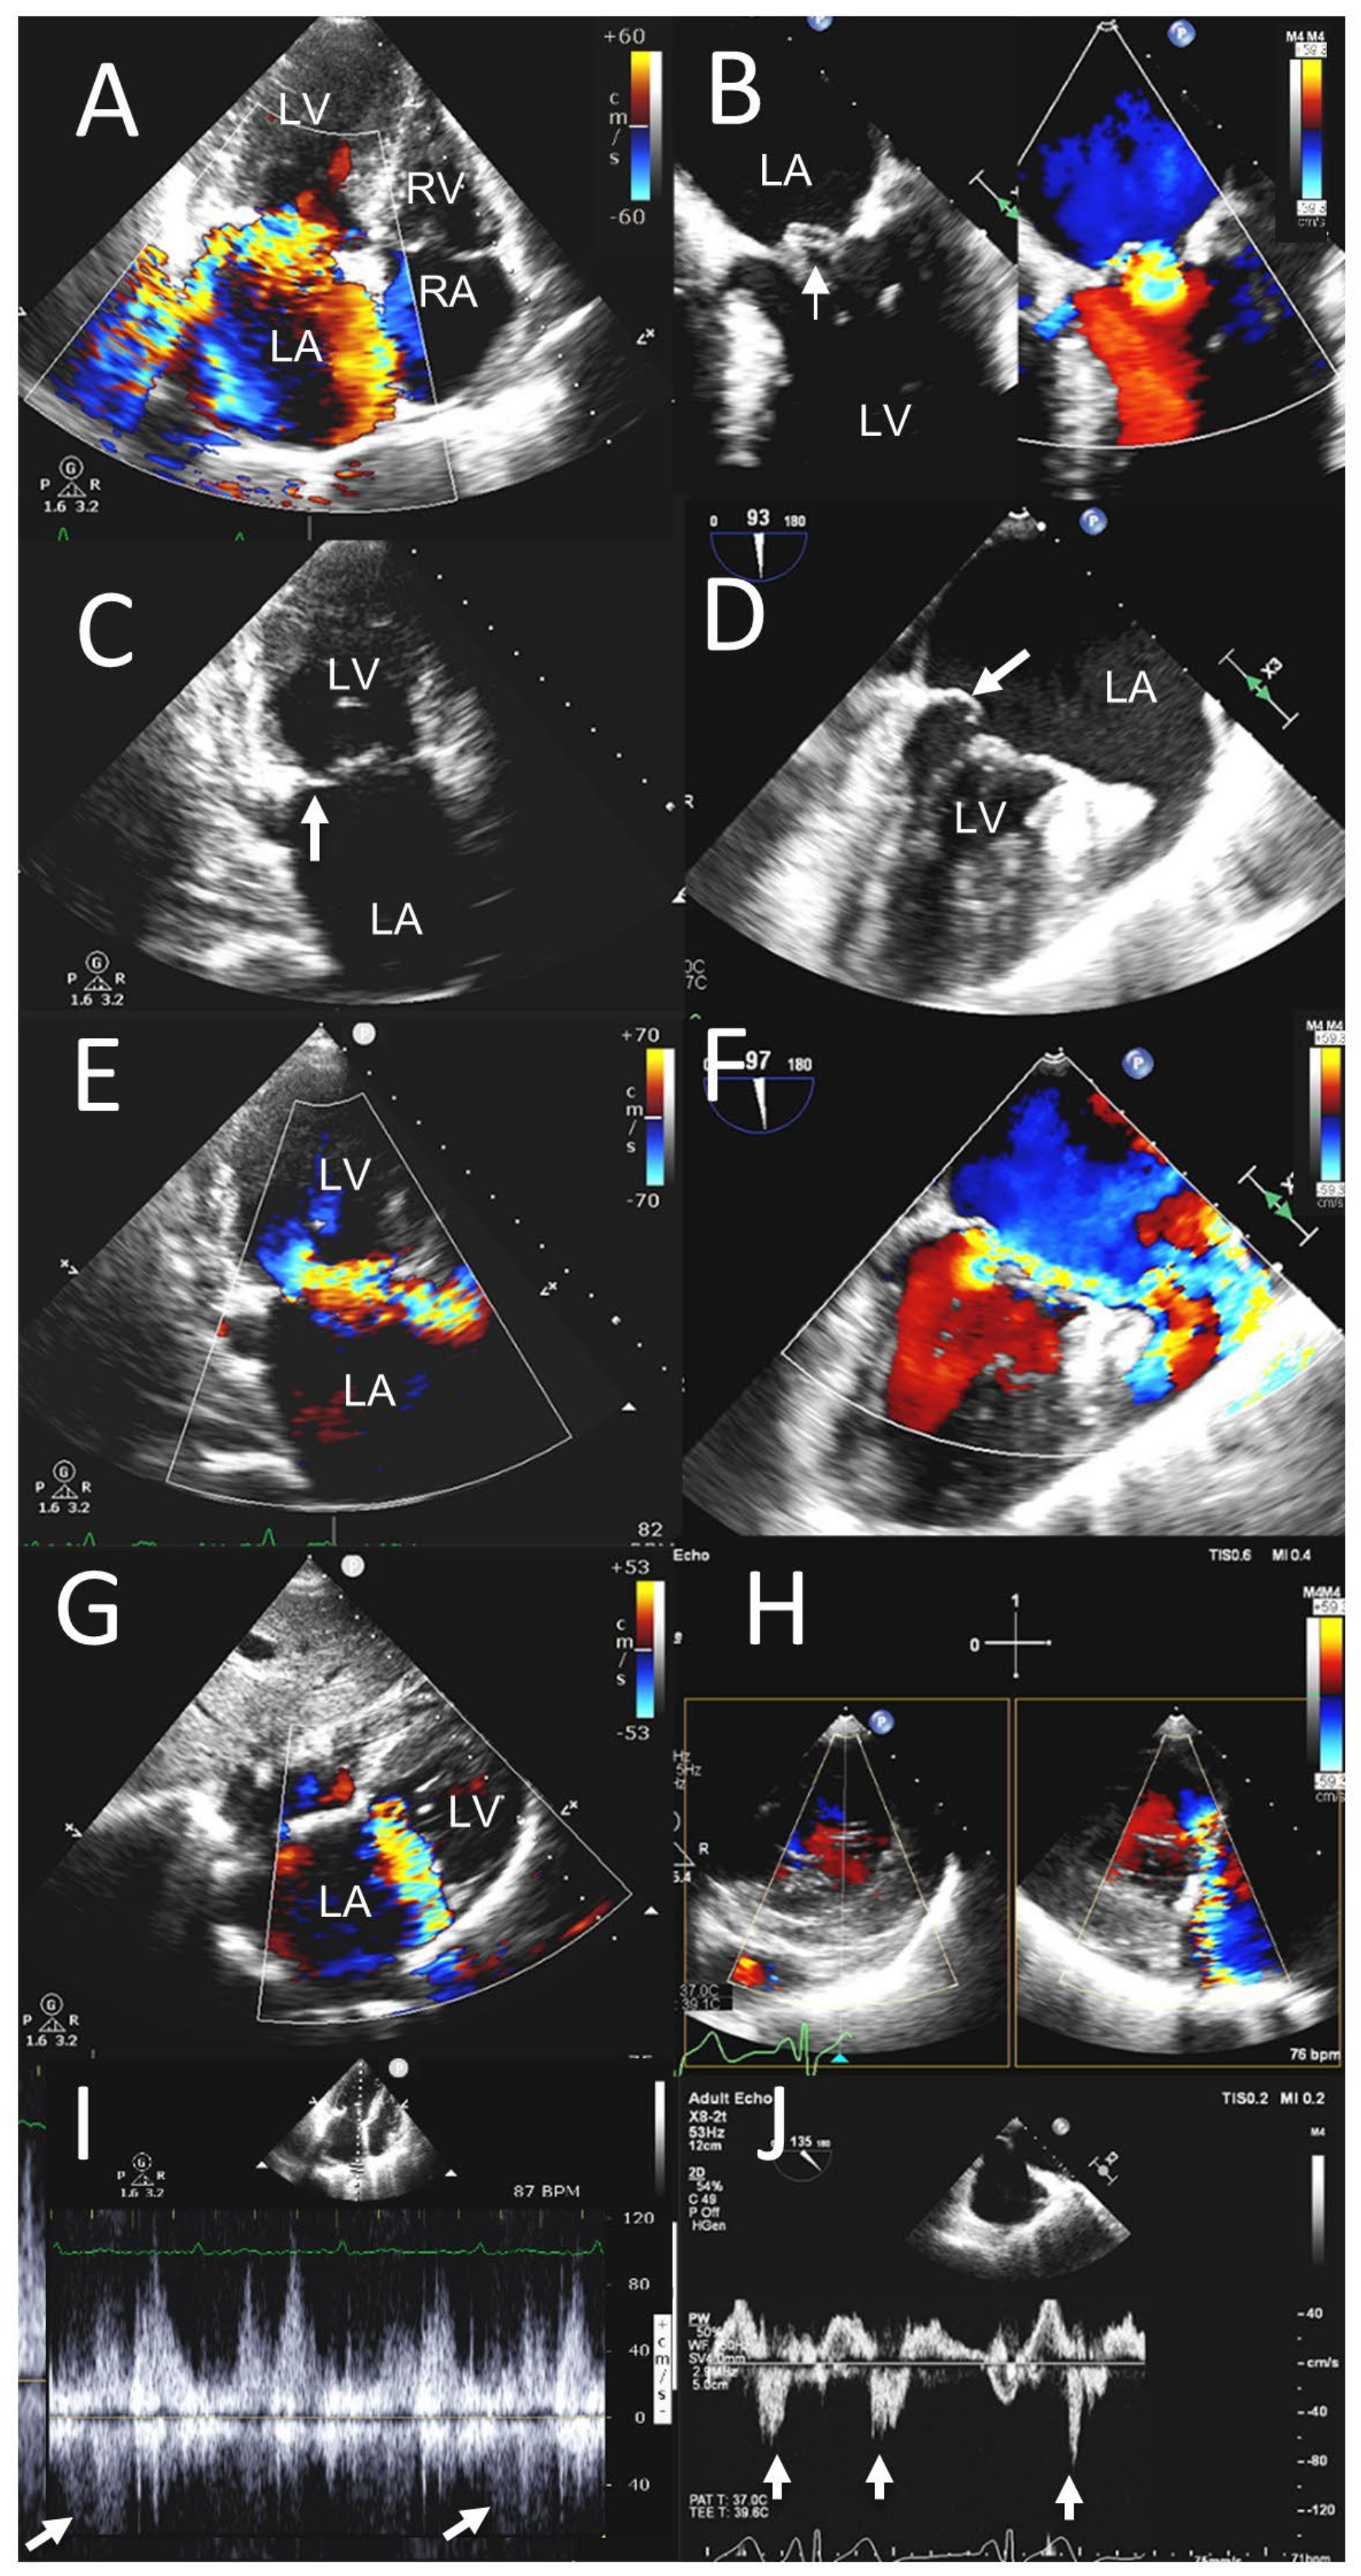

3.2. ≥Moderate Valvular Regurgitation

| Mitral regurgitation | 16 (20.8) | 17 (22.1) |

| Aortic regurgitation | 10 (13.0) | 11 (14.3) |

| Aortic stenosis | 15 (19.5) | 18 (23.4) |

| Tricuspid regurgitation | 13 (16.9) | 14 (18.2) |

| Paravalvular leak on MV | 2 (2.6) | 2 (2.6) |

| Paravalvular leak on AV | 2 (2.6) | 2 (2.6) |

| Aortic prosthetic valve stenosis | 1 (1.3) | 1 (1.3) |